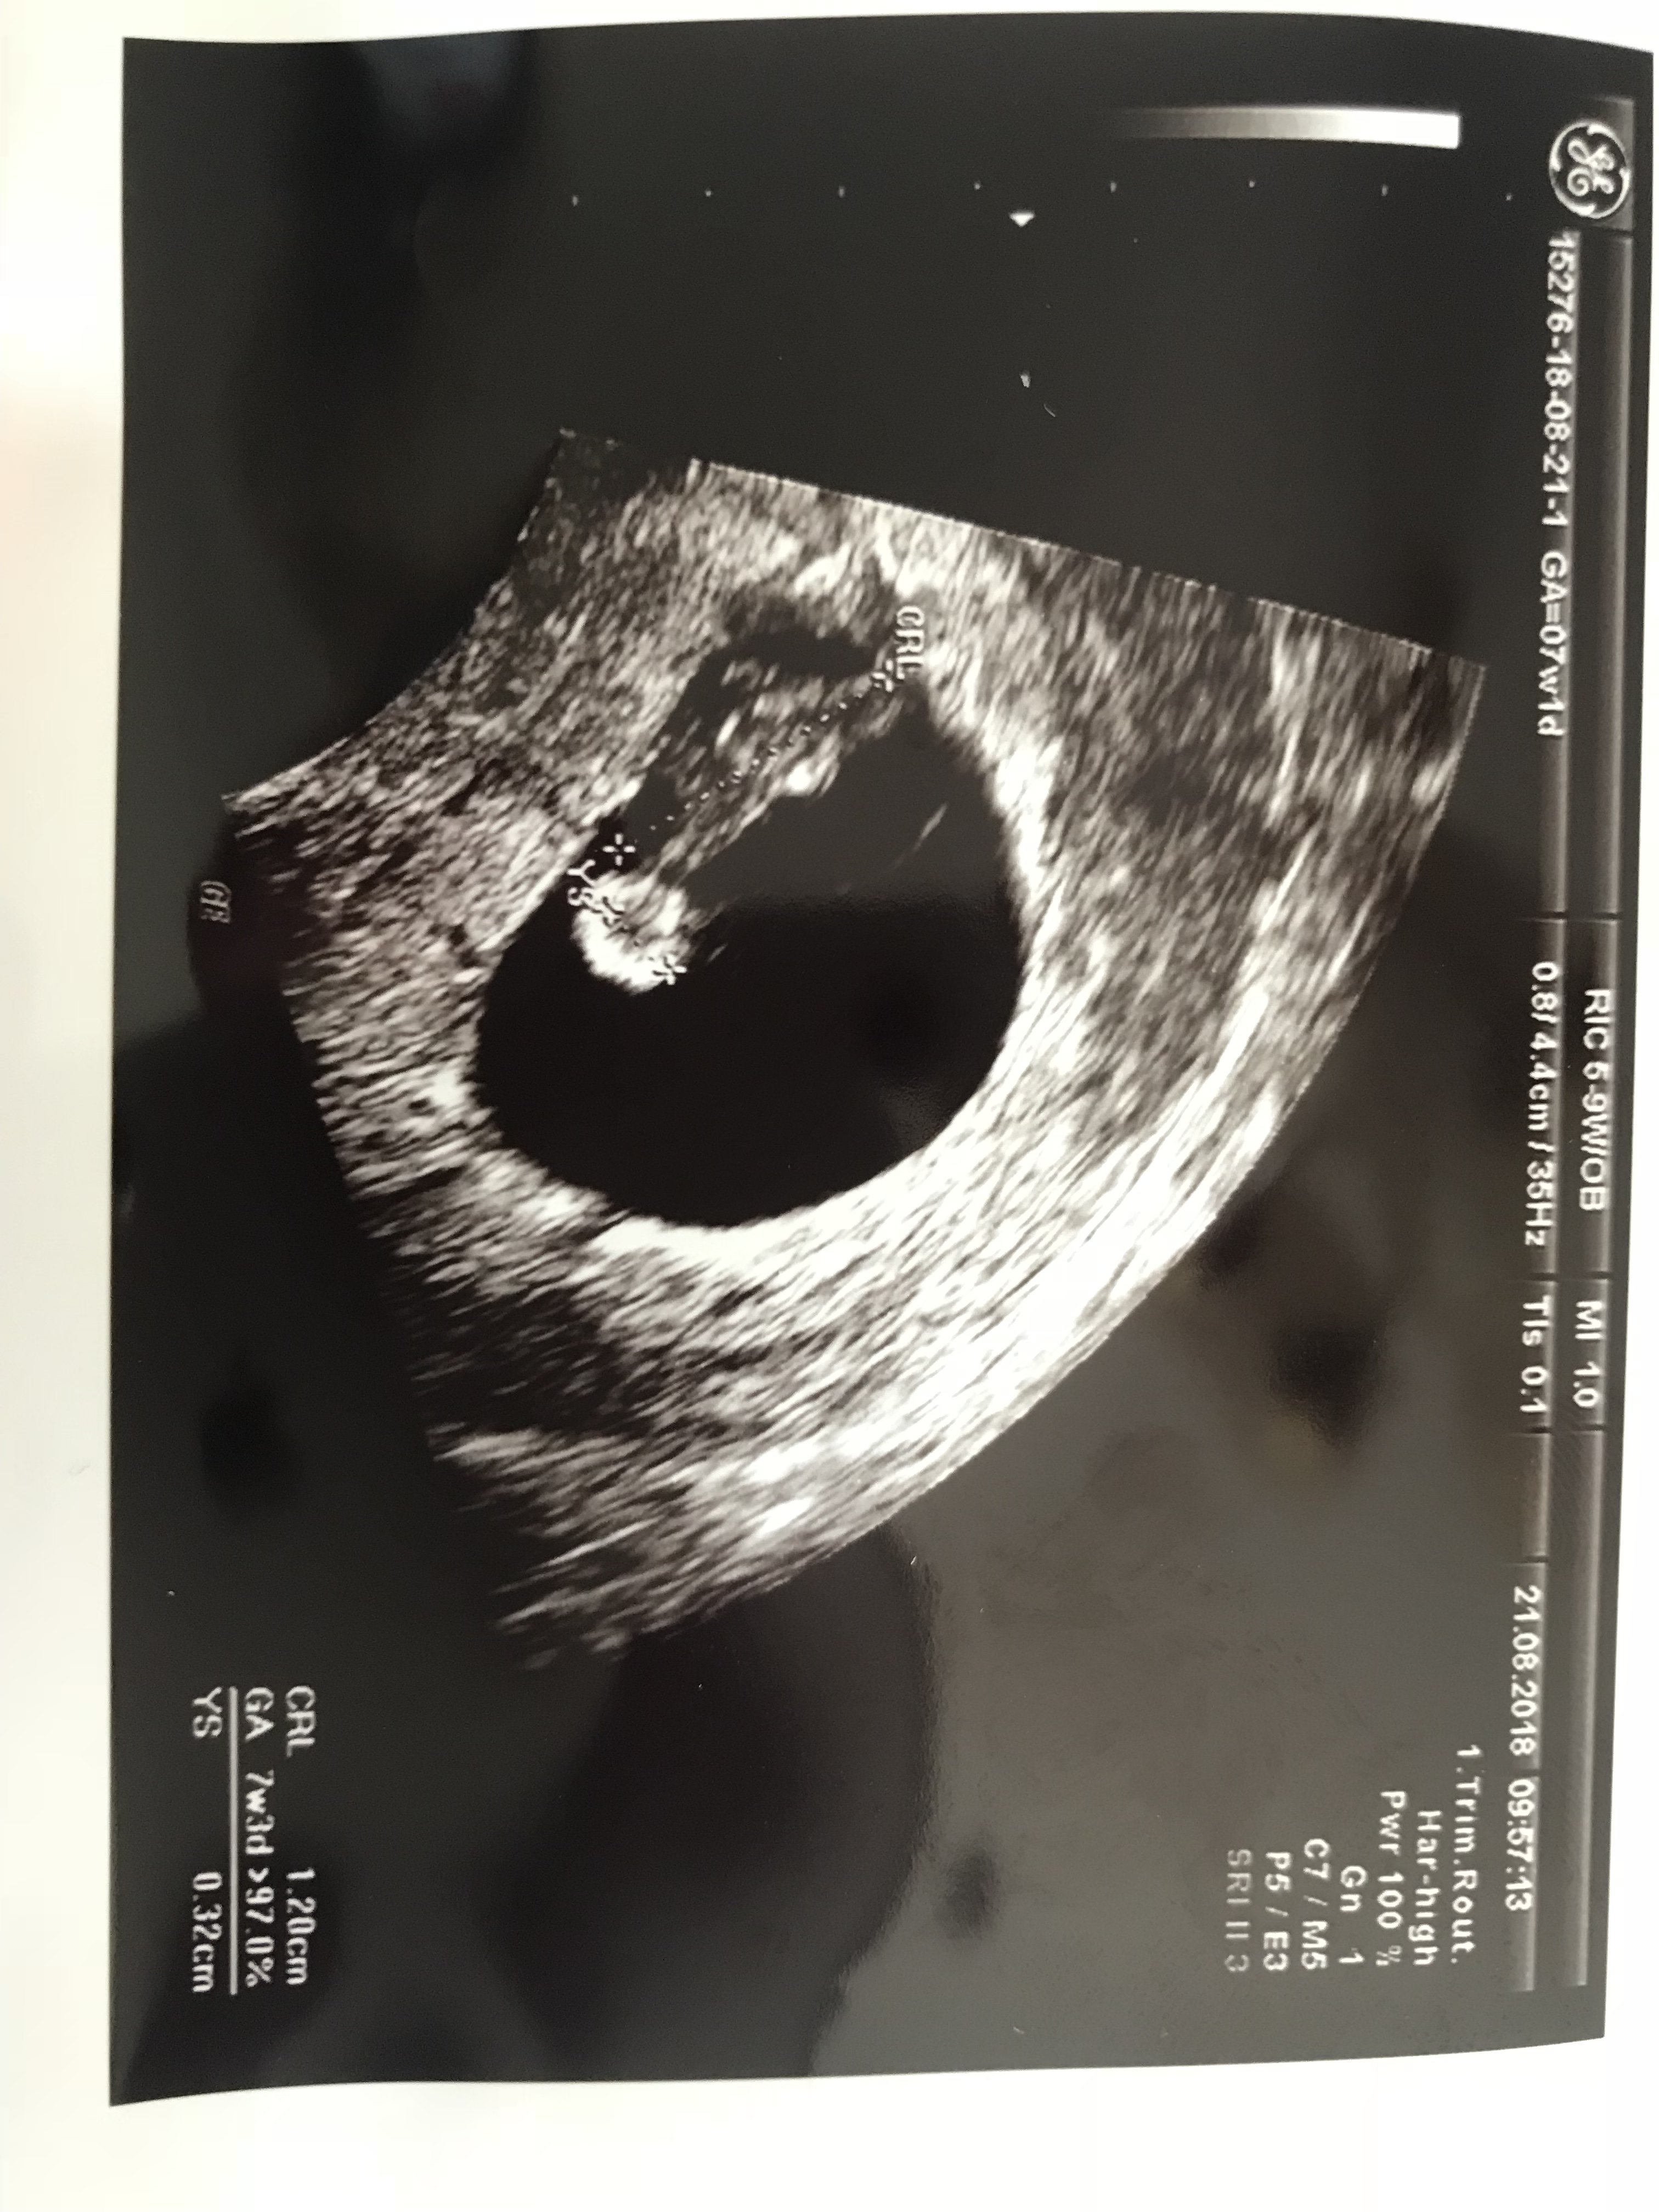

U nas jest wszystko dobrze serduszko bije 7tydzien 1 dzień według okresu a według usg 7tydzien 3 dzień jest mały krwiaczek ale mam się nim nie martwić może się wchłonąć albo pęknąć i może być plamienie albo brudzenie aby się nie martwić a termin na 6 albo 8 kwietnia i założył już mi kartę ciąży i dał na badania muszę zrobić badania mocz morfologię glukozę i następna wizyta 19 września ;)